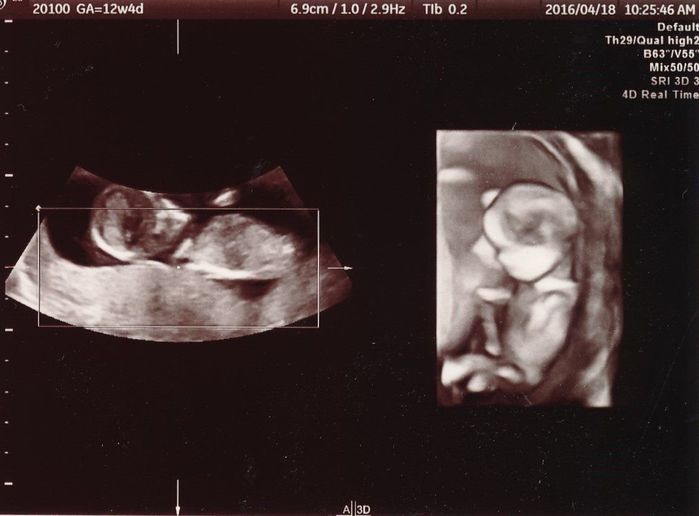

妊娠12週目のエコー写真

こちらの写真では、赤ちゃんの心拍が写っています。頭が左で体が右です。食事内容や生活習慣に加えて、仕事量が多くなりすぎないように気をつけていました。

こちらの写真では、頭と体、手足が分かります。両足の付け根の辺りから上に向かって伸びているのがへその緒で、自分とのつながりが写真で見えて何だか不思議な気持ちになりました。

こちらは4Dの拡大版です。先ほどの写真よりも、へその緒のねじれている感じが少しですが読み取れます。